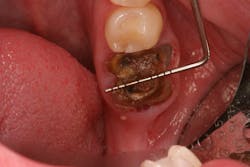

• Rebuild defects around adjacent teeth after extracting teeth due to periodontal disease (figures 5a–5c)

This surgical video demonstrates removal of a tooth with loss of buccal plate and grafting of the remaining socket with Geistlich Bio-Oss Collagen and Geistlich Bio-Gide to preserve the ridge for implant placement.